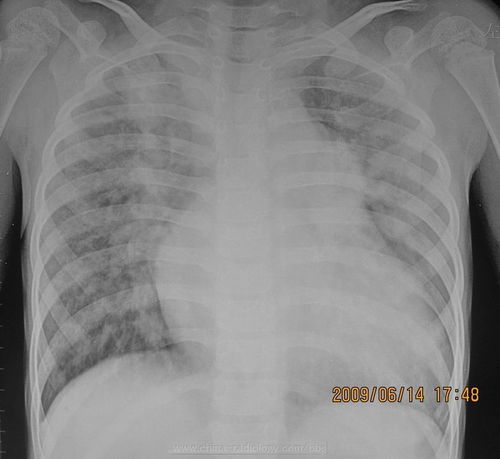

胸透可以看到胸部的軟組織、骨骼(包括胸椎)、縱隔(心臟、大血管、氣管、食管等)、氣管和支氣、胸膜、肺組織等??梢栽\斷肺和氣管的先天性疾病,如發(fā)育異常、肺部的各種炎癥、急慢性支氣管炎、比較明顯的支氣管擴(kuò)張癥、肺氣腫或肺水腫、各型肺結(jié)核、肺腫瘤、胸腔積液、氣胸、縱隔腫瘤、心臟形態(tài)異常等

健康查體最常做的是胸部的X線檢查,最基本的就是胸透。 胸透可以看到胸部的軟組織、骨骼(包括胸椎)、縱隔(心臟、大血管、氣管、食管等)、氣管和支氣、胸膜、肺組織等。

可以診斷肺和氣管的先天性疾病,如發(fā)育異常、肺部的各種炎癥、急慢性支氣管炎、比較明顯的支氣管擴(kuò)張癥、肺氣腫或肺水腫、各型肺結(jié)核、肺腫瘤、胸腔積液、氣胸、縱隔腫瘤、心臟形態(tài)異常等。